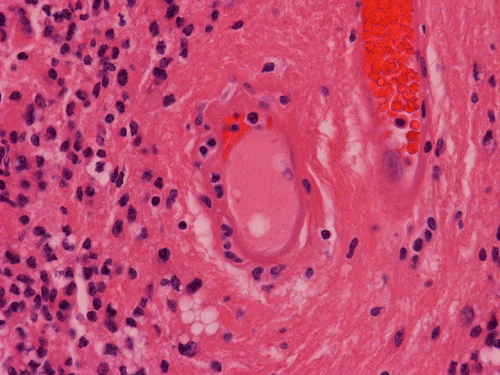

Pathology of the Case: MRI shows a large mass with the more solid component located in the lateral ventricles and the cystic component protruding into the cortical area. The solid area is enhanced (Panel A). On low magnification, the lesion has alternating area of high and low cellularity (Panel B) with scattered calcifications in some of the sections. Medium and high magnification demonstrates perivascular coronary arrangement of cytoplasmic processes (Panel C, D, and E). The nuclei are bland and mitotic figures are not readily seen. Randomly scattered brown pigment containing cells are found in multiple areas of the tumor (Panel F, G, and H). Scant lipidized cells with enlarged nuclei (Panel I) are also present. The tumor cells are strongly positive for glial fibrillary acidic protein (GFAP) (Panel J and K) and S100 protein but are negative for epithelial membrane antigen (EMA), neurofilament proteins, and NeuN. The overall Ki67 labeling is low but focal small areas (about the size of one high power field) has increased labeling. The pigment appears to be melanin on microscopic examination. These pigments are positive with Fontana-Masson stain (Panel L) but negative for Prussian blue stain for iron (Panel M). These features confirmed that these are melanin pigments. The pigment granules are positive for periodic acid-Schiff reaction (N), negative for Ziehl-Neelsen (acid fast) stain..

Ependymal rosettes are tiny lumina spaces lined by epithelial-like cells. These tumor cells blend imperceptibly with the surrounding tumor cells.  Although highly characteristics, ependymal rosettes are quite uncommon and are typically found in infratentorial tumors. When they are slightly larger, they may be called ependymal canals. It is important to not that these rosettes or canals do not have any basement membrane, a key feature not to mistaken these structures as metastatic carcinomas.